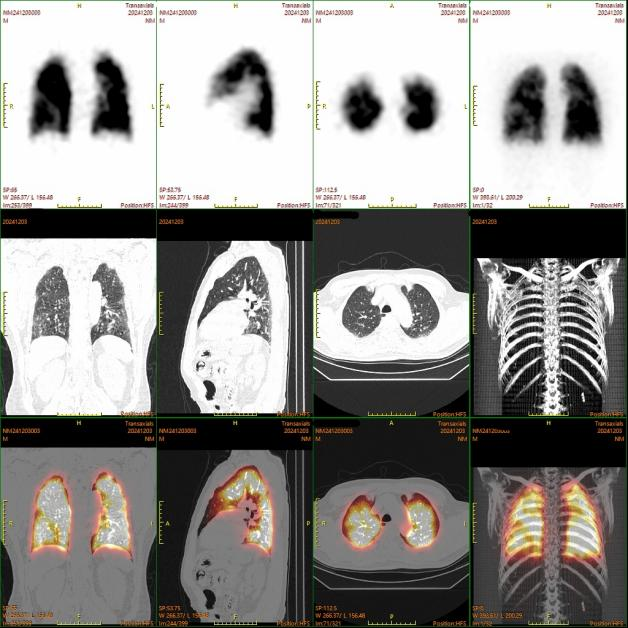

双肺平面显像

图片

双肺SPECT/CT断层融合显像